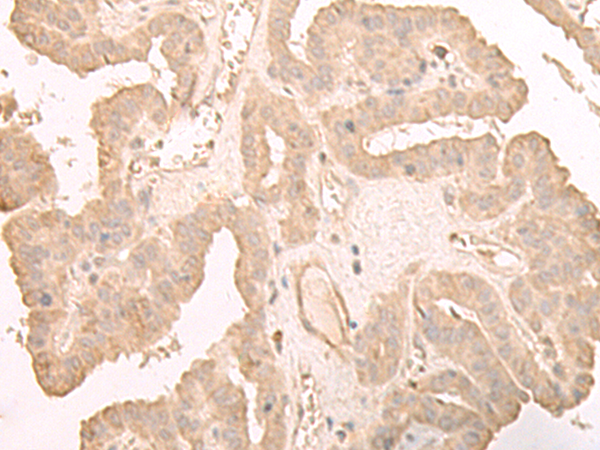

分类: 科研抗体货号: P09813别名: 39K2; 39K3应用: IHC反应种属: Human, Mouse, Rat